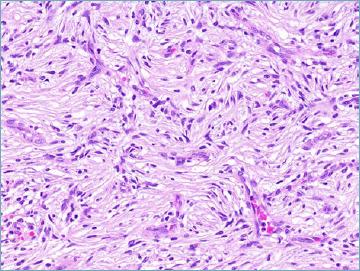

Mesenchymal tumours represent one of the most challenging field of diagnostic pathology and refinement of classification schemes plays a key role in improving the quality of pathologic diagnosis and, as a consequence, of therapeutic options. The recent publication of the new WHO classification of Soft Tissue Tumours and Bone represents a major step toward improved standardization of diagnosis. Importantly, the 2020 WHO classification has been opened to expert clinicians that have further contributed to underline the key value of pathologic diagnosis as a rationale for proper treatment. Several relevant advances have been introduced. In the attempt to improve the prediction of clinical behaviour of solitary fibrous tumour, a risk assessment scheme has been implemented. NTRK-rearranged soft tissue tumours are now listed as an "emerging entity" also in consideration of the recent therapeutic developments in terms of NTRK inhibition. This decision has been source of a passionate debate regarding the definition of "tumour entity" as well as the consequences of a "pathology agnostic" approach to precision oncology. In consideration of their distinct clinicopathologic features, undifferentiated round cell sarcomas are now kept separate from Ewing sarcoma and subclassified, according to the underlying gene rearrangements, into three main subgroups (CIC, BCLR and not ETS fused sarcomas) Importantly, In order to avoid potential confusion, tumour entities such as gastrointestinal stroma tumours are addressed homogenously across the different WHO fascicles. Pathologic diagnosis represents the integration of morphologic, immunohistochemical and molecular characteristics and is a key element of clinical decision making. The WHO classification is as a key instrument to promote multidisciplinarity, stimulating pathologists, geneticists and clinicians to join efforts aimed to translate novel pathologic findings into more effective treatments.